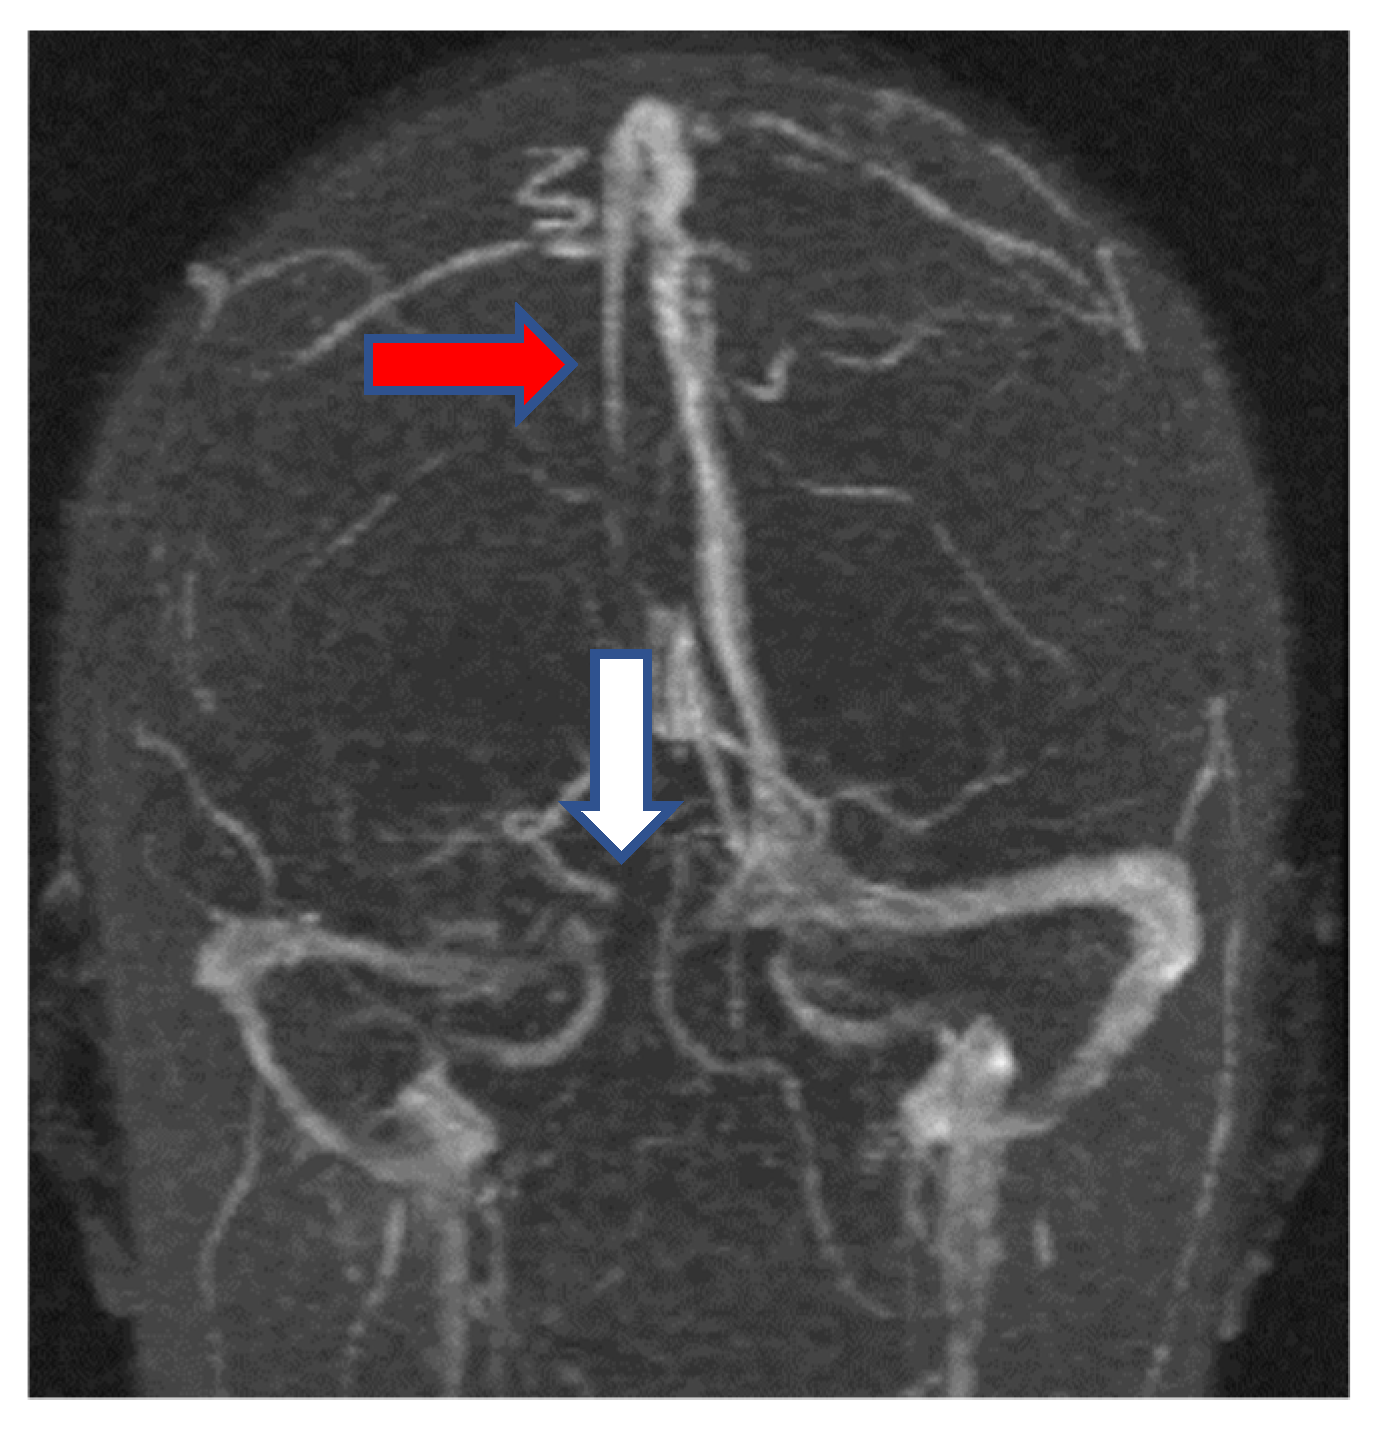

2.1.3. Neuroimaging

- Jianu, D.C.; Jianu, S.N.; Motoc, A.G.; Poenaru, M.; Petrica, L.; Vlad, A.; Ursoniu, S.; Gogu, A.E.; Dan, F.T. Diagnosis and management of a young women with isolated lateral sinus thrombosis. Rom. J. Morphol. Embryol. 2017, 58, 1515–1518. [Google Scholar] [PubMed]